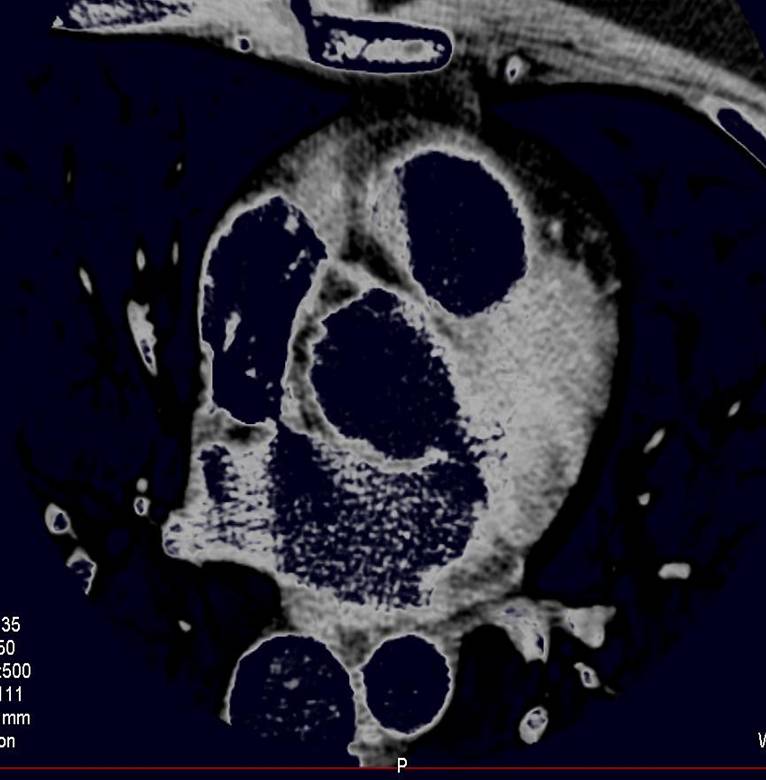

The non-invasive imaging modality of multi-detector computed tomography has dramatically evolved the last ten years and that is due to hardware and software developments. The newer generation of scanners allows increased spatial and temporal resolution that improves the clinical reliability giving further insights into the evaluation of coronary artery disease. Heart morphology imaging followed by studies of myocardial function and assessment of cardiac valves can be performed from the information derived from the data of the coronary artery examination. Also, the venous anatomy of the heart, coronary artery bypass grafts, stents, and cardiac tumors can be imaged and evaluated when necessary. For the beneficial use of this method, entrance criteria for different patient groups need to be set in order to allow improved outcome of multi-detector CT.